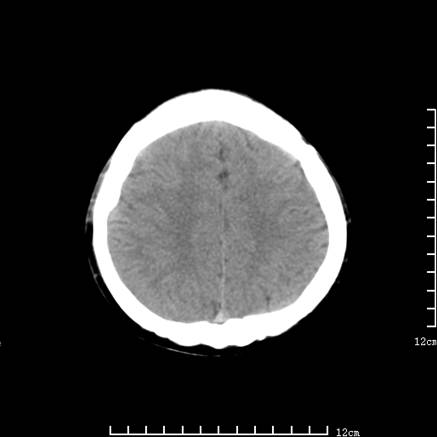

以下是引用jiajie在2008-9-5 22:25:00的发言:[br]男,22岁,头痛1月余。脑室、脑池内病变ct值约-120hu。[br][br]双侧侧脑室内低密度影充填,出现脑脊液脂肪平面,脑池内亦可见弥散分布的斑点状低密度影,脑室脑池未见明显扩大。[br]考虑胆脂瘤破裂后内容物进入脑脊液。